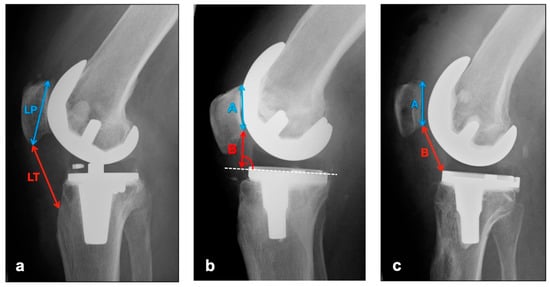

The images in lateral projection with knee flexion between 30° and 45° (dependent on patient compliance and experience of technical assistant) were used to assess vertical positional deviations of the patella cranially (patella alta) or caudally (patella infera). Three different indices were measured (see Figure 1).

The Insall–Salvati Index, which is largely independent from the joint position, is calculated as the quotient of the distance between the poles of the patella and the length of the ligamentum patellae from the caudal patellar pole to the insertion at the tibial tuberosity [17]. Normal range is 0.8–1.2 [18].

Instead of the pole distance, the Blackburne–Peel Index measures the articulating surface of the patella and relates it to a perpendicular from the lower pole of the patellar articulating surface to the tibial plateau [19]. Normal range is 0.6–1 [18].

The Caton–Deschamps Index is measured in a similar way, but instead of the previously described perpendicular, the distance from the caudal pole of the patellar articulation surface to the ventrocranial boundary edge of the tibia is measured and set in relation to the patellar articulation surface [20]. Normal range is 0.6–1.2 [18].

Figure 1. Measurement of patellar height with (a) Insall–Salvati Index (Quotient LT/LP), (b) Blackburne–Peel Index (Quotient B/A), (c) Caton–Deschamps Index (Quotient B/A).